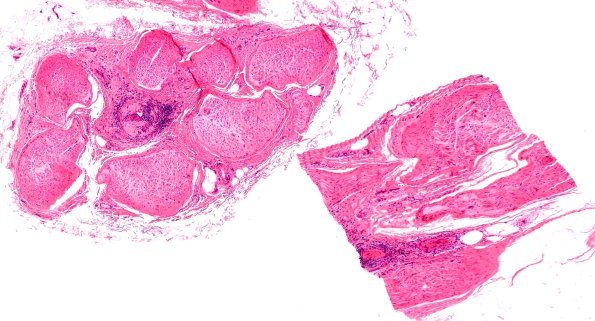

Washington University Experience | PERIPHERAL NEUROPATHY | 11 VASCULITIS - VASCULOPATHY | 4 Polyarteritis nodosa | 7A1 PAN (Case 7) H&E 4X

Case 7 History ---- The patient is a 63 year old woman with possible neuritis. Clinical diagnosis is mononeuritis multiplex. Operative procedure: Left gastrocnemius and left sural nerve biopsies. ---- 7A1,2 This vessel shows fibrinoid vascular necrosis with partial thrombosis and several recanalized channels (arrows). (H&E)